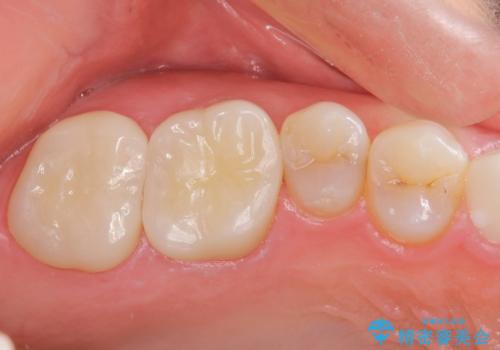

根っこの感染 再治療をしてかぶせ物を製作する

根管治療を丁寧に仕上げることで、長く安心してかぶせ物を使っていただくことができます。

かぶせものの種類:Bellezza